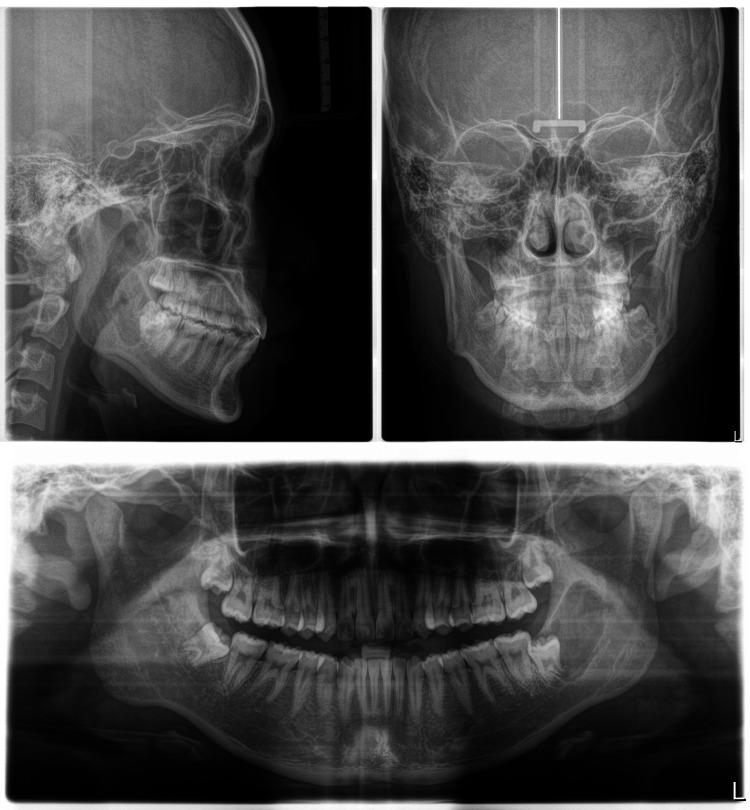

Clear aligner therapy has significantly improved orthodontic treatment by offering patients a more aesthetically pleasing option compared to traditional braces. This literature review and case report specifically focus on the effectiveness of directly printed clear aligners in treating Class II malocclusions and crowding. Class II malocclusions are characterized by excessive overjet, which often results from skeletal or dental discrepancies between the upper and lower jaws. Crowding refers to the lack of space for teeth within the dental arch, leading to misalignment and potential functional issues. The review and case report highlight the increasing importance of directly printed clear aligners in modern orthodontics and provide clinicians with a valuable tool to effectively address complex malocclusions and crowding while also meeting patient needs for discretion and comfort. Further research is necessary to validate the long-term stability and outcomes of directly printed clear aligner therapy in various orthodontic cases. A detailed case report demonstrates the successful treatment of a patient with Class II malocclusion and mild crowding using directly printed clear aligners. Treatment outcomes include improvements in dental alignment, occlusion, and facial aesthetics, showcasing the effectiveness of this innovative approach.

与传统牙套相比,隐形矫治器疗法为患者提供了更美观的选择,显著改善了正畸治疗。这篇文献综述和病例报告特别关注直接打印的隐形矫治器在治疗II类错颌畸形和牙列拥挤方面的有效性。II类错颌畸形的特征是覆盖过大,这通常是由于上下颌之间的骨骼或牙齿差异所致。牙列拥挤是指牙弓内牙齿缺乏空间,导致牙齿排列不齐和潜在的功能问题。该综述和病例报告强调了直接打印的隐形矫治器在现代正畸学中日益重要的地位,并为临床医生提供了一种有价值的工具,既能有效解决复杂的错颌畸形和牙列拥挤问题,又能满足患者对美观和舒适的需求。有必要进行进一步的研究,以验证直接打印的隐形矫治器疗法在各种正畸病例中的长期稳定性和治疗效果。一份详细的病例报告展示了使用直接打印的隐形矫治器成功治疗一名II类错颌畸形和轻度牙列拥挤患者的过程。治疗结果包括牙齿排列、咬合和面部美观的改善,展示了这种创新方法的有效性。